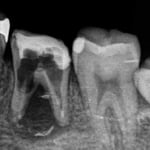

#穿孔修復(遠心根の近心壁)

大臼歯の遠心根の近心壁に大きな穿孔が生じていた症例です。

近心根の根尖部の透過像も消失。

遠心は、頬側、舌側ともに弯曲が強く、根管を探すのに苦労し、途中であきらめかけましたが、なんとか目標を達成できました。

治療には2年の時間がかかりました。(1回/月)今なら、もっと治療時間を短縮できると思いますが、患者さんもあきらめることなく、通院してくれました。

術後、4年経過していますが、問題なく機能しています。

治療期間:約24ケ月(経過観察期間8ケ月を含む)

治療回数:20回(1~2回/月)

治療費:28万円(穿孔歯修復+根管治療+支台築造+補綴)※毎回の処置料は別途

リスク:再治療は困難なこと。(そもそも抜歯の症例)

※リスクはどのような治療にも必ずあること。